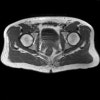

- Axial section

Axial T1 large field of view allows for evaluation of both hips simultaneously, particularly the acetabulae.

Axial PD fat suppressed is sensitive to fluid that may be present with avascular necrosis or stress fractures, while maintaining high a SNR.